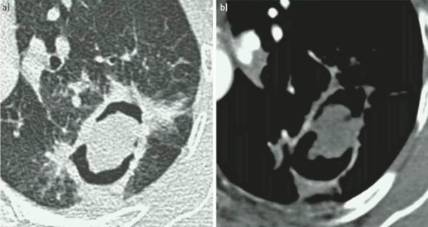

慢性空洞性肺曲霉病(CCPA):最常见,单发或多发的肺空洞(薄壁或厚壁),空洞内可包含一个或多个曲菌球或不规则的腔内物质,具有曲霉菌血清学和微生物学依据,并有明显肺部和全身症状,至少3个多月的观察有放射影像学进展(新发空洞,空洞外周浸润增加及纤维增生增加)。

亚急性侵袭性肺曲霉病(SAIA):轻度免疫缺陷的侵袭性肺曲霉病患者,发生在1-3个月内,具有可变的影像学特征,包括空洞、结节、有“脓肿形成的进展性实变”。最重要的特征为肺组织发现菌丝,另血液或呼吸液GM试验呈强阳性。